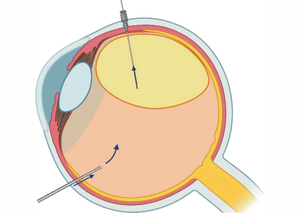

Видалення підвивихнутого кришталика

Видалення підвивихнутого кришталика або факофрагментація уламків ядра, вивихнутих у скловидне тіло — це складна офтальмологічна хірургічна процедура, яка використовується для лікування підвивиху (сублюксації) або вивиху (люксації) кришталика, коли частина або весь кришталик зміщується з його нормального положення в оці.

Екструзія силікону

Екструзія силікону — це ускладнення, яке може виникнути після введення силіконової олії в око для лікування певних офтальмологічних захворювань, таких як відшарування сітківки. У випадках, коли екструзія значна або викликає серйозні ускладнення, може знадобитися повторна операція для видалення силіконової олії або зміцнення оболонок ока. Іноді проводять процедуру знову, замінюючи силікон іншими матеріалами або коригуючи його кількість.

Операція з приводу відшарування сітківки

Операція з приводу відшарування сітківки — це хірургічне втручання, спрямоване на відновлення нормального положення сітківки на задній стінці ока. Відшарування сітківки є серйозним офтальмологічним захворюванням, яке може призвести до втрати зору, якщо його не лікувати.